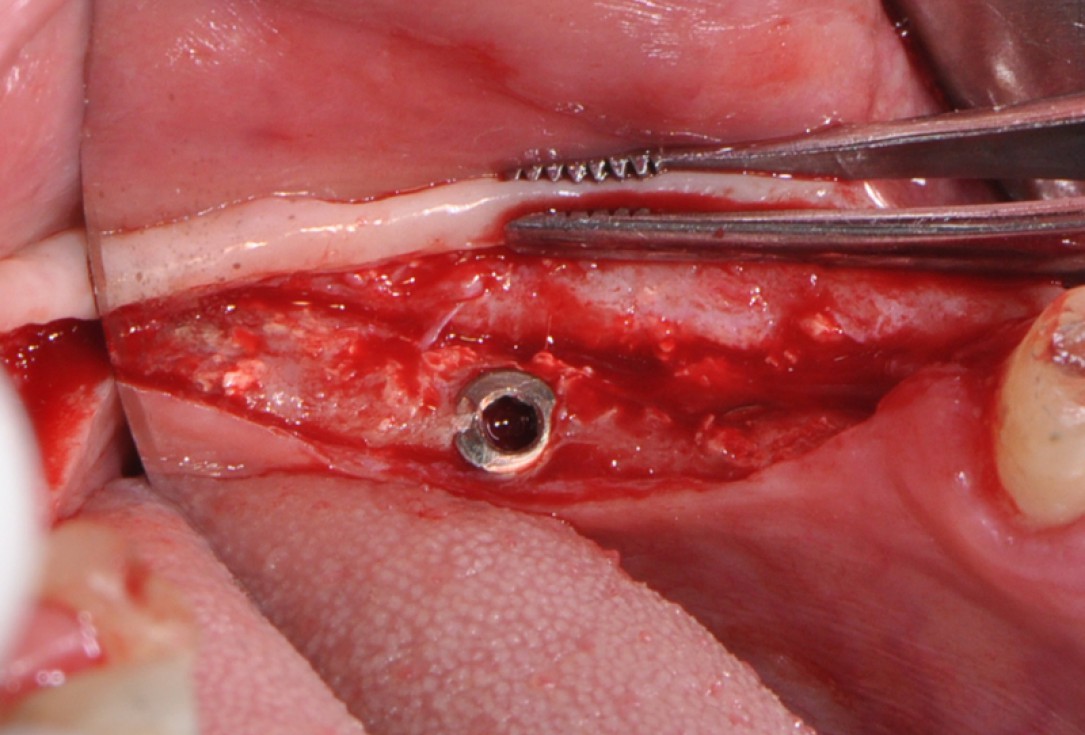

botiss cerabone® & Jason® membrane for GBR - Clinical case by Dr. S. Kovalevsky

Implant insertion in atrophic alveolar ridge